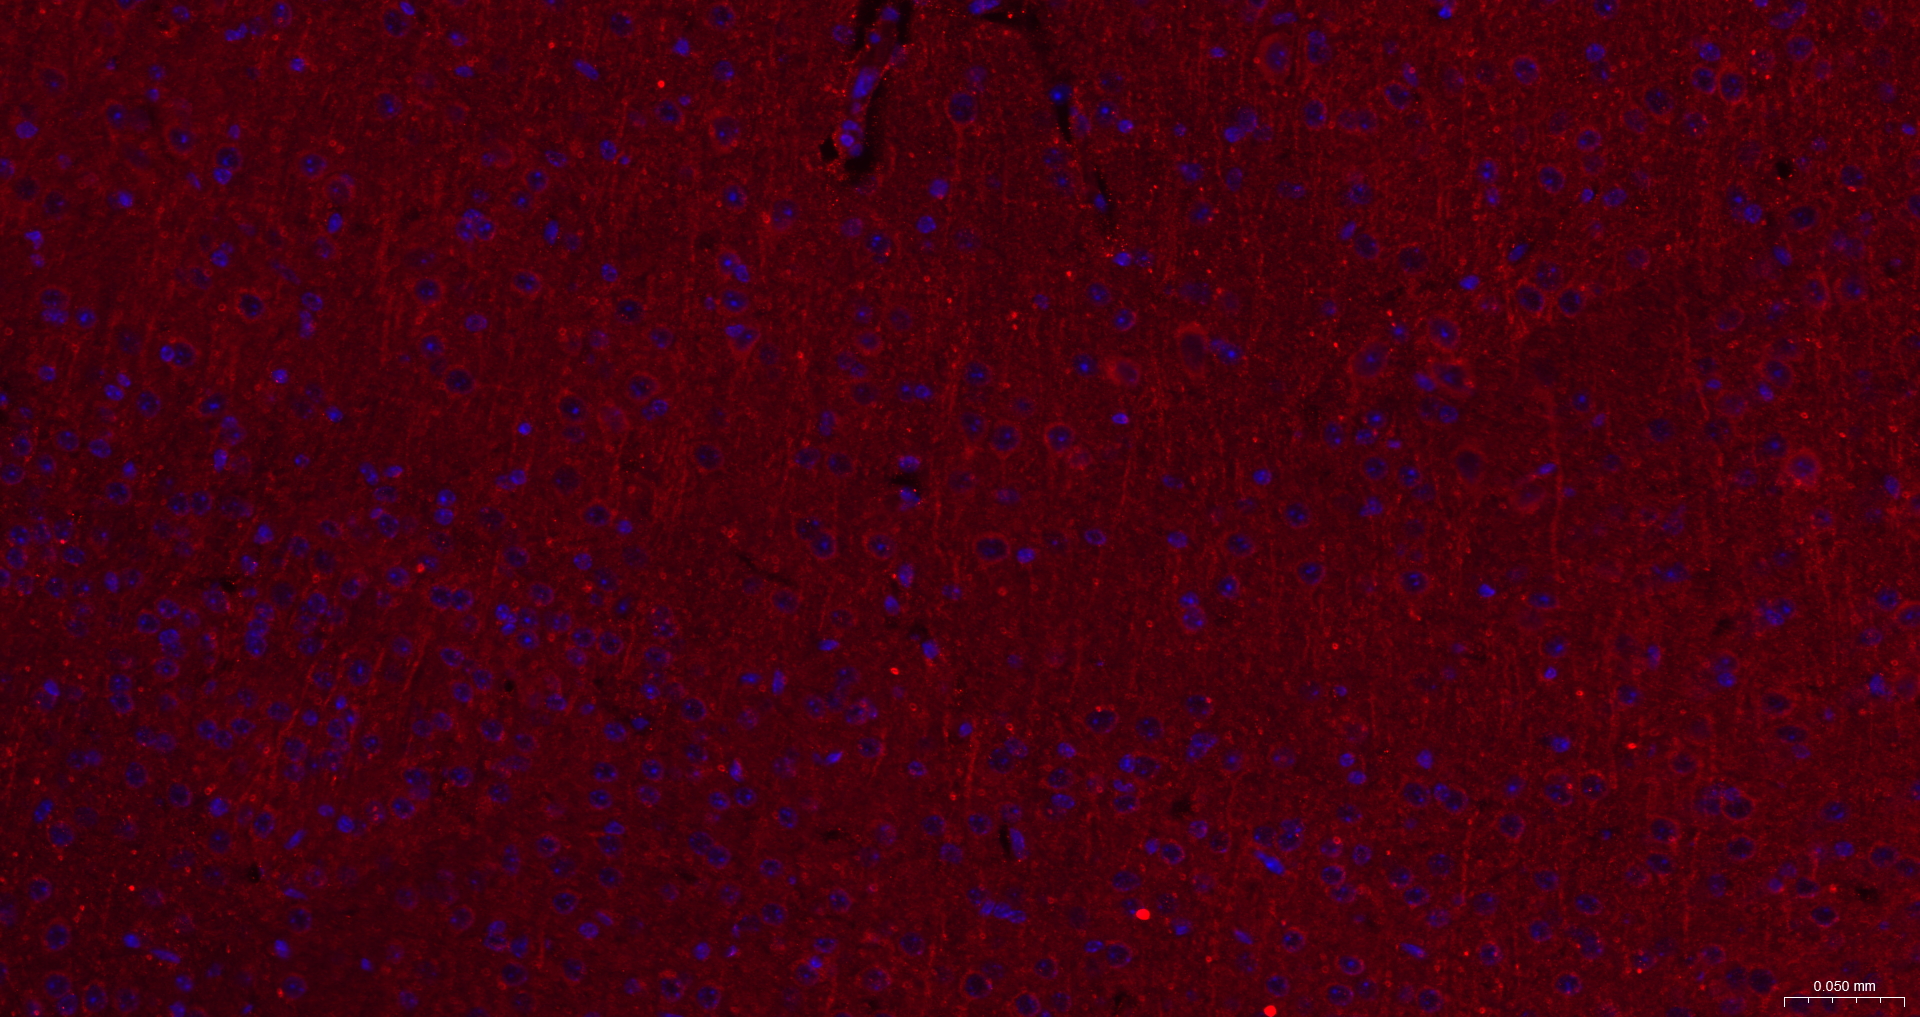

Presenilin 1 Recombinant Antibody

• IHC-F

• IF

IHC-F 1:100-500